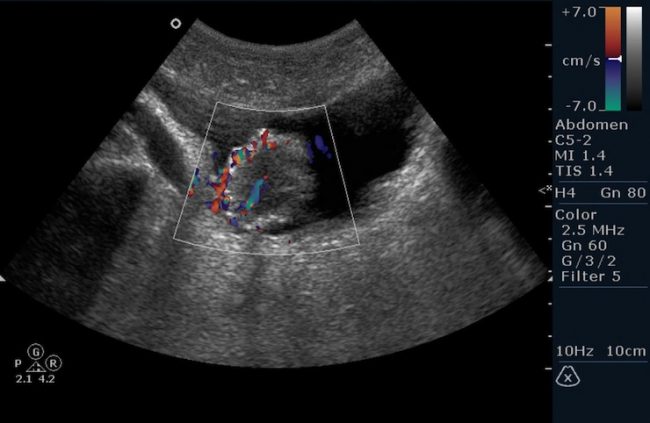

При подозрении на патологию в обязательном порядке назначается ультразвуковое исследование. Оно позволяет выявить место расположения опухоли, оценить ее размер и исключить метастазирование.